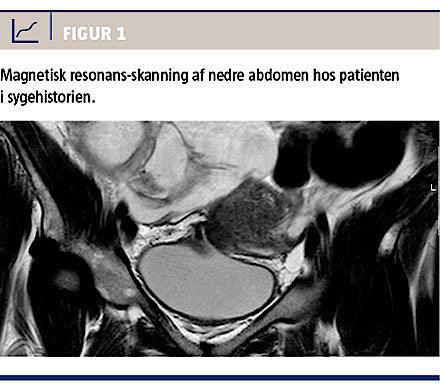

På en urologisk afdeling behandlede man en 32-årig kvinde med dette syndrom. Fire måneder efter at have fået foretaget et kejsersnit, blev hun henvist til et sygehus pga. hæmaturi og urin per vaginam. Primær mistanke var en vesikovaginal fistel. Dette blev bekræftet ved installation af methylenblåt i blæren, hvorefter man så blå farve i fornix posterior. Senere undersøgelser med CT-urografi og -cystografi bekræftede ikke denne diagnose. Knap et år efter kejsersnit blev hun henvist til OUH til videre udredning og behandling. Man havde endnu ikke visualiseret en fistel, og patienten var nu meget påvirket af symptomerne i sin hverdag med urinafgang per vaginam og makroskopisk hæmaturi under menstruation. Ved cystoskopi og magnetisk resonans-(MR)-skanning (Figur 1) blev der fundet en fistel mellem vesica og uterus. Fistlen i blæren blev excideret, og uterus blev fjernet efter patientens ønske. Hun blev udskrevet i velbefindende.